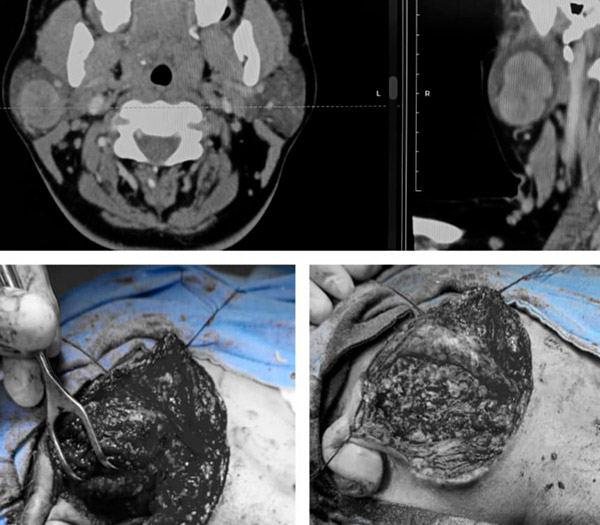

Procedimientos Misceláneos

Tratamiento integral de diversas patologías quirúrgicas con enfoque multidisciplinario

Manejamos fascitis necrosante, infecciones necrosantes de tejidos blandos, gangrena, quistes pilonidales, sebáceos, queratínicos y epidermoides, lipomas cervicales, y colocación de catéteres Tenckhoff para diálisis peritoneal. También tratamos gastroenteritis bacteriana con complicaciones quirúrgicas.